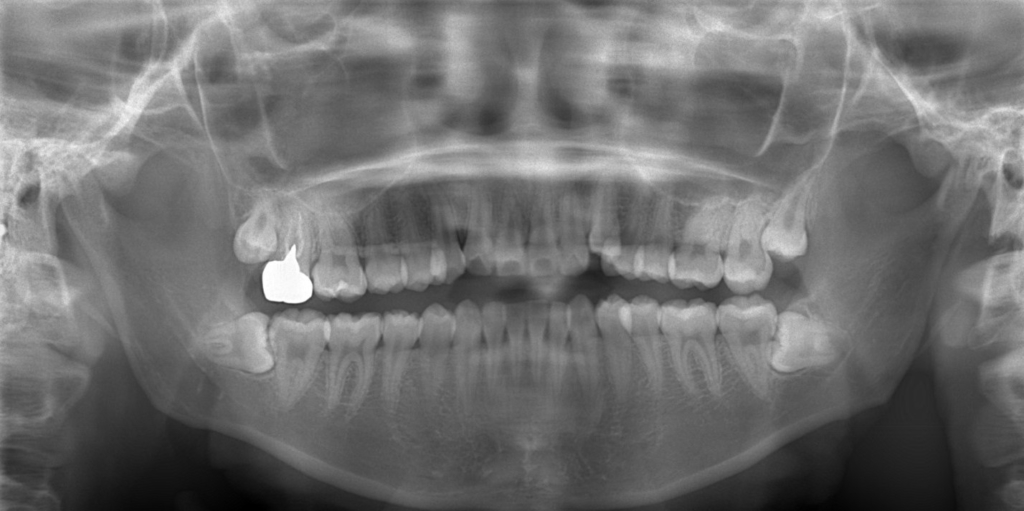

レントゲン写真で確認すると、

この患者さんの場合、

【診断】

#1.上下顎前突

#2.歯と顎の不調和による叢生(軽度)

と診断しました。